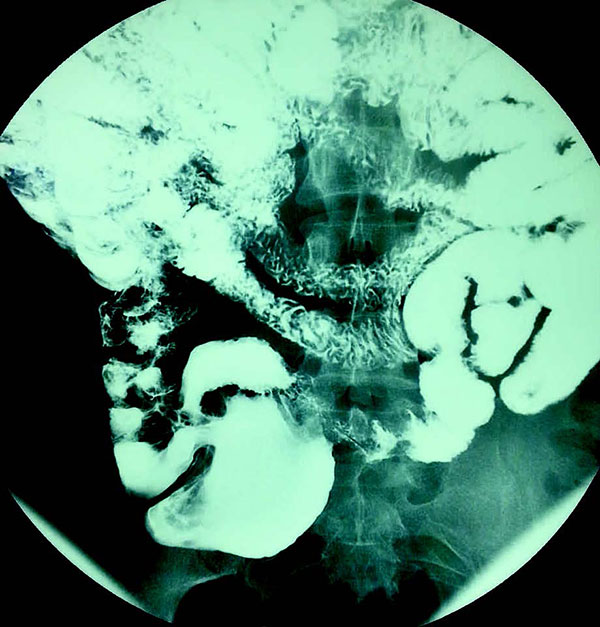

患者男,32岁。12岁时被诊断为复发性鼻窦炎、支气管炎和扁桃体炎。患者自述腹泻2周余。影像学示结节性淋巴组织增生:

下列哪种疾病可出现这些特殊的影像学图片?

答案:B